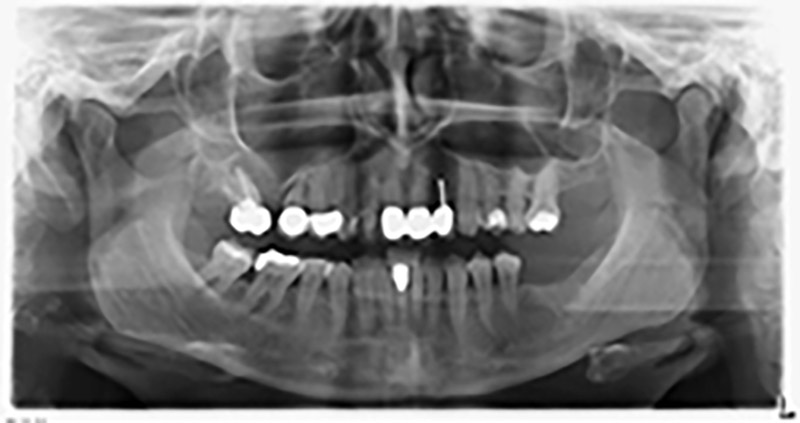

Die 59-jährige Patientin wurde mit einer fortgeschrittenen Parodontitis vorstellig, beschrieb ein ungutes Gefühl und einen schlechten Geschmack ausgehend vom ersten Quadranten distal. Die klinische Untersuchung zeigte allgemein erhöhte Taschentiefen und einen stark fortgeschrittenen Knochenabbau in regio 16 und 14. Die radiologische Untersuchung untermauerte den Befund (Abb. 1). Die Zähne 16 und 14 waren nicht zu erhalten.

Etwa sechs Monate nach Extraktion der Zähne 16 und 14 wurde zur Planung und Risikominimierung eine digitale Volumentomografie (DVT, Planmeca) erstellt. Hierbei wurde deutlich, dass der Knochen sich nicht in der gewünschten Quantität regeneriert hat (Abb. 2 bis 7).